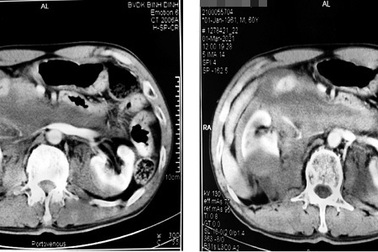

Hiếm gặp trường hợp thận móng ngựa bị phình động mạch chủ bụngNgày 30/5, nguồn tin từ Bệnh viện Đa khoa TP Cần Thơ cho biết, các bác sĩ khoa Ngoại lồng ngực và Ngoại niệu Bệnh viện Đa khoa TP Cần Thơ vừa phối hợp phẫu thuật cấp cứu cho một bệnh nhân 68 tuổi, bị phình động mạch chủ bụng bóc tách và có thận hình móng ngựa.